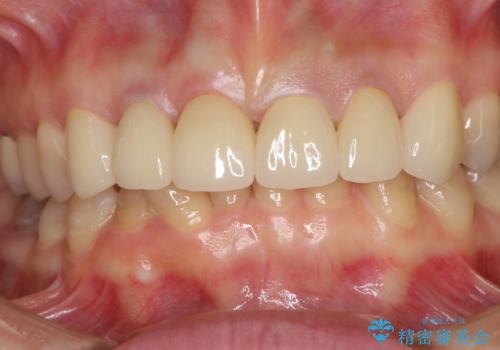

深い虫歯の犬歯は、根管治療を行った後に部分矯正を行い、歯周外科処置により環境を整えてから、6歯それぞれのオールセラミッククラウンにて補綴することとしました。

下の前歯がほとんど隠れてしまうほどの深い咬み合わせで、咬合力も強いため、治療期間中は仮歯が外れやすく、ご迷惑をおかけしました。

セラミッククラウン装着後は、とても自然な口元に仕上がりました。